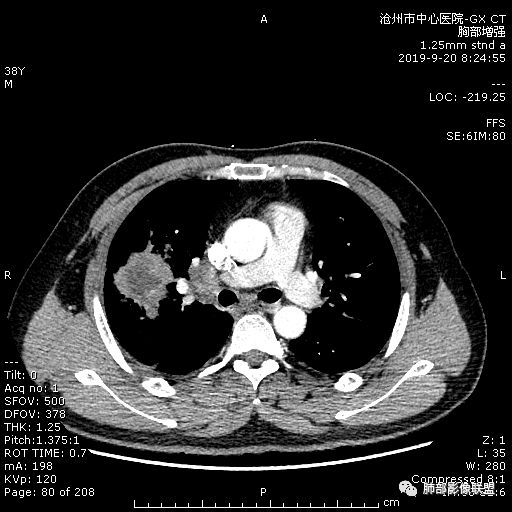

年轻男性,咳嗽2月,痰中带血,胸痛,炎症指标稍高,肿标正常。影像,右肺上叶不规则团块影,浅分叶,伴边界不清磨玻璃影,从外周向内分布,局部胸膜增厚,病灶中央坏死,坏死边界尚清,空洞形成,空洞内壁光滑;考虑炎性肉芽肿性病变,结核可能,鉴别恶性肿瘤及真菌感染。病灶分布特点不考虑隐球。

38岁,男性,慢性咳嗽2月,右胸痛8天,无发热;白细胞高,肿瘤标志物不高;右上肺不规则块状影,周围有磨玻璃影,边界清,整体有膨胀感,分叶,与胸膜糊墙,并见栽赃,增强肿块中央坏死,周边强化。综合考虑,考虑恶性,鳞癌可能。

38岁,男性,慢性咳嗽2月,右胸痛8天,无发热。白细胞高,肿瘤标志物不高。右上肺不规则块状影,周围有磨玻璃影,边界模糊,整体有膨胀感,分叶,与胸膜糊墙,可疑栽赃,增强肿块中央坏死,边界清,周边强化明显,强化区有低密度影,壁不规则,跨叶生长,支气管截断,伴支气管扩张,综合考虑腺癌

中年男性,咳嗽2月,伴胸痛8天,少许痰血,无发热中性粒明显增高,低氧,肿标不高,右肺上叶不规则实性肿块,深分叶,局部凹陷呈月牙铲改变,多坏死,多空泡,前段支气管分支似见堵塞,2R、4R、10R和7区淋巴结肿大。考虑肺癌可能,建议支气管镜活检

3.ct表现:肺脓肿可呈结节状或团块状,有时呈不规则形,气道来源肺脓肿常单发,血行来源常多发,边缘模糊,部分病灶周围可见片状肺实变及磨玻璃影;病灶中央为液化坏死区,若脓肿与支气管相通,脓液排出可形成空洞,空洞内可形成液平;急性肺脓肿内壁多不规则;慢性肺脓肿洞壁较厚,一般不规则或形成多房空洞:CT增强扫描空洞壁可见强化,空洞壁为纤维肉芽组织,呈典型的环形强化;慢性肺脓肿周围可有较广泛的纤维索条影,可伴支气管扩张.肺

今天病例坏死周围也可以看到明显强化的脓肿壁,只是局部脓肿壁不规则模糊,部分脓肿壁规则清楚。